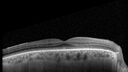

Acute Retinal Pigment Epitheliitis (Krills disease)2 views15 year old with sudden central vision loss in one eye. The vision loss persisted though for at least 6 months (which may be a laser injury)Apr 13, 2026